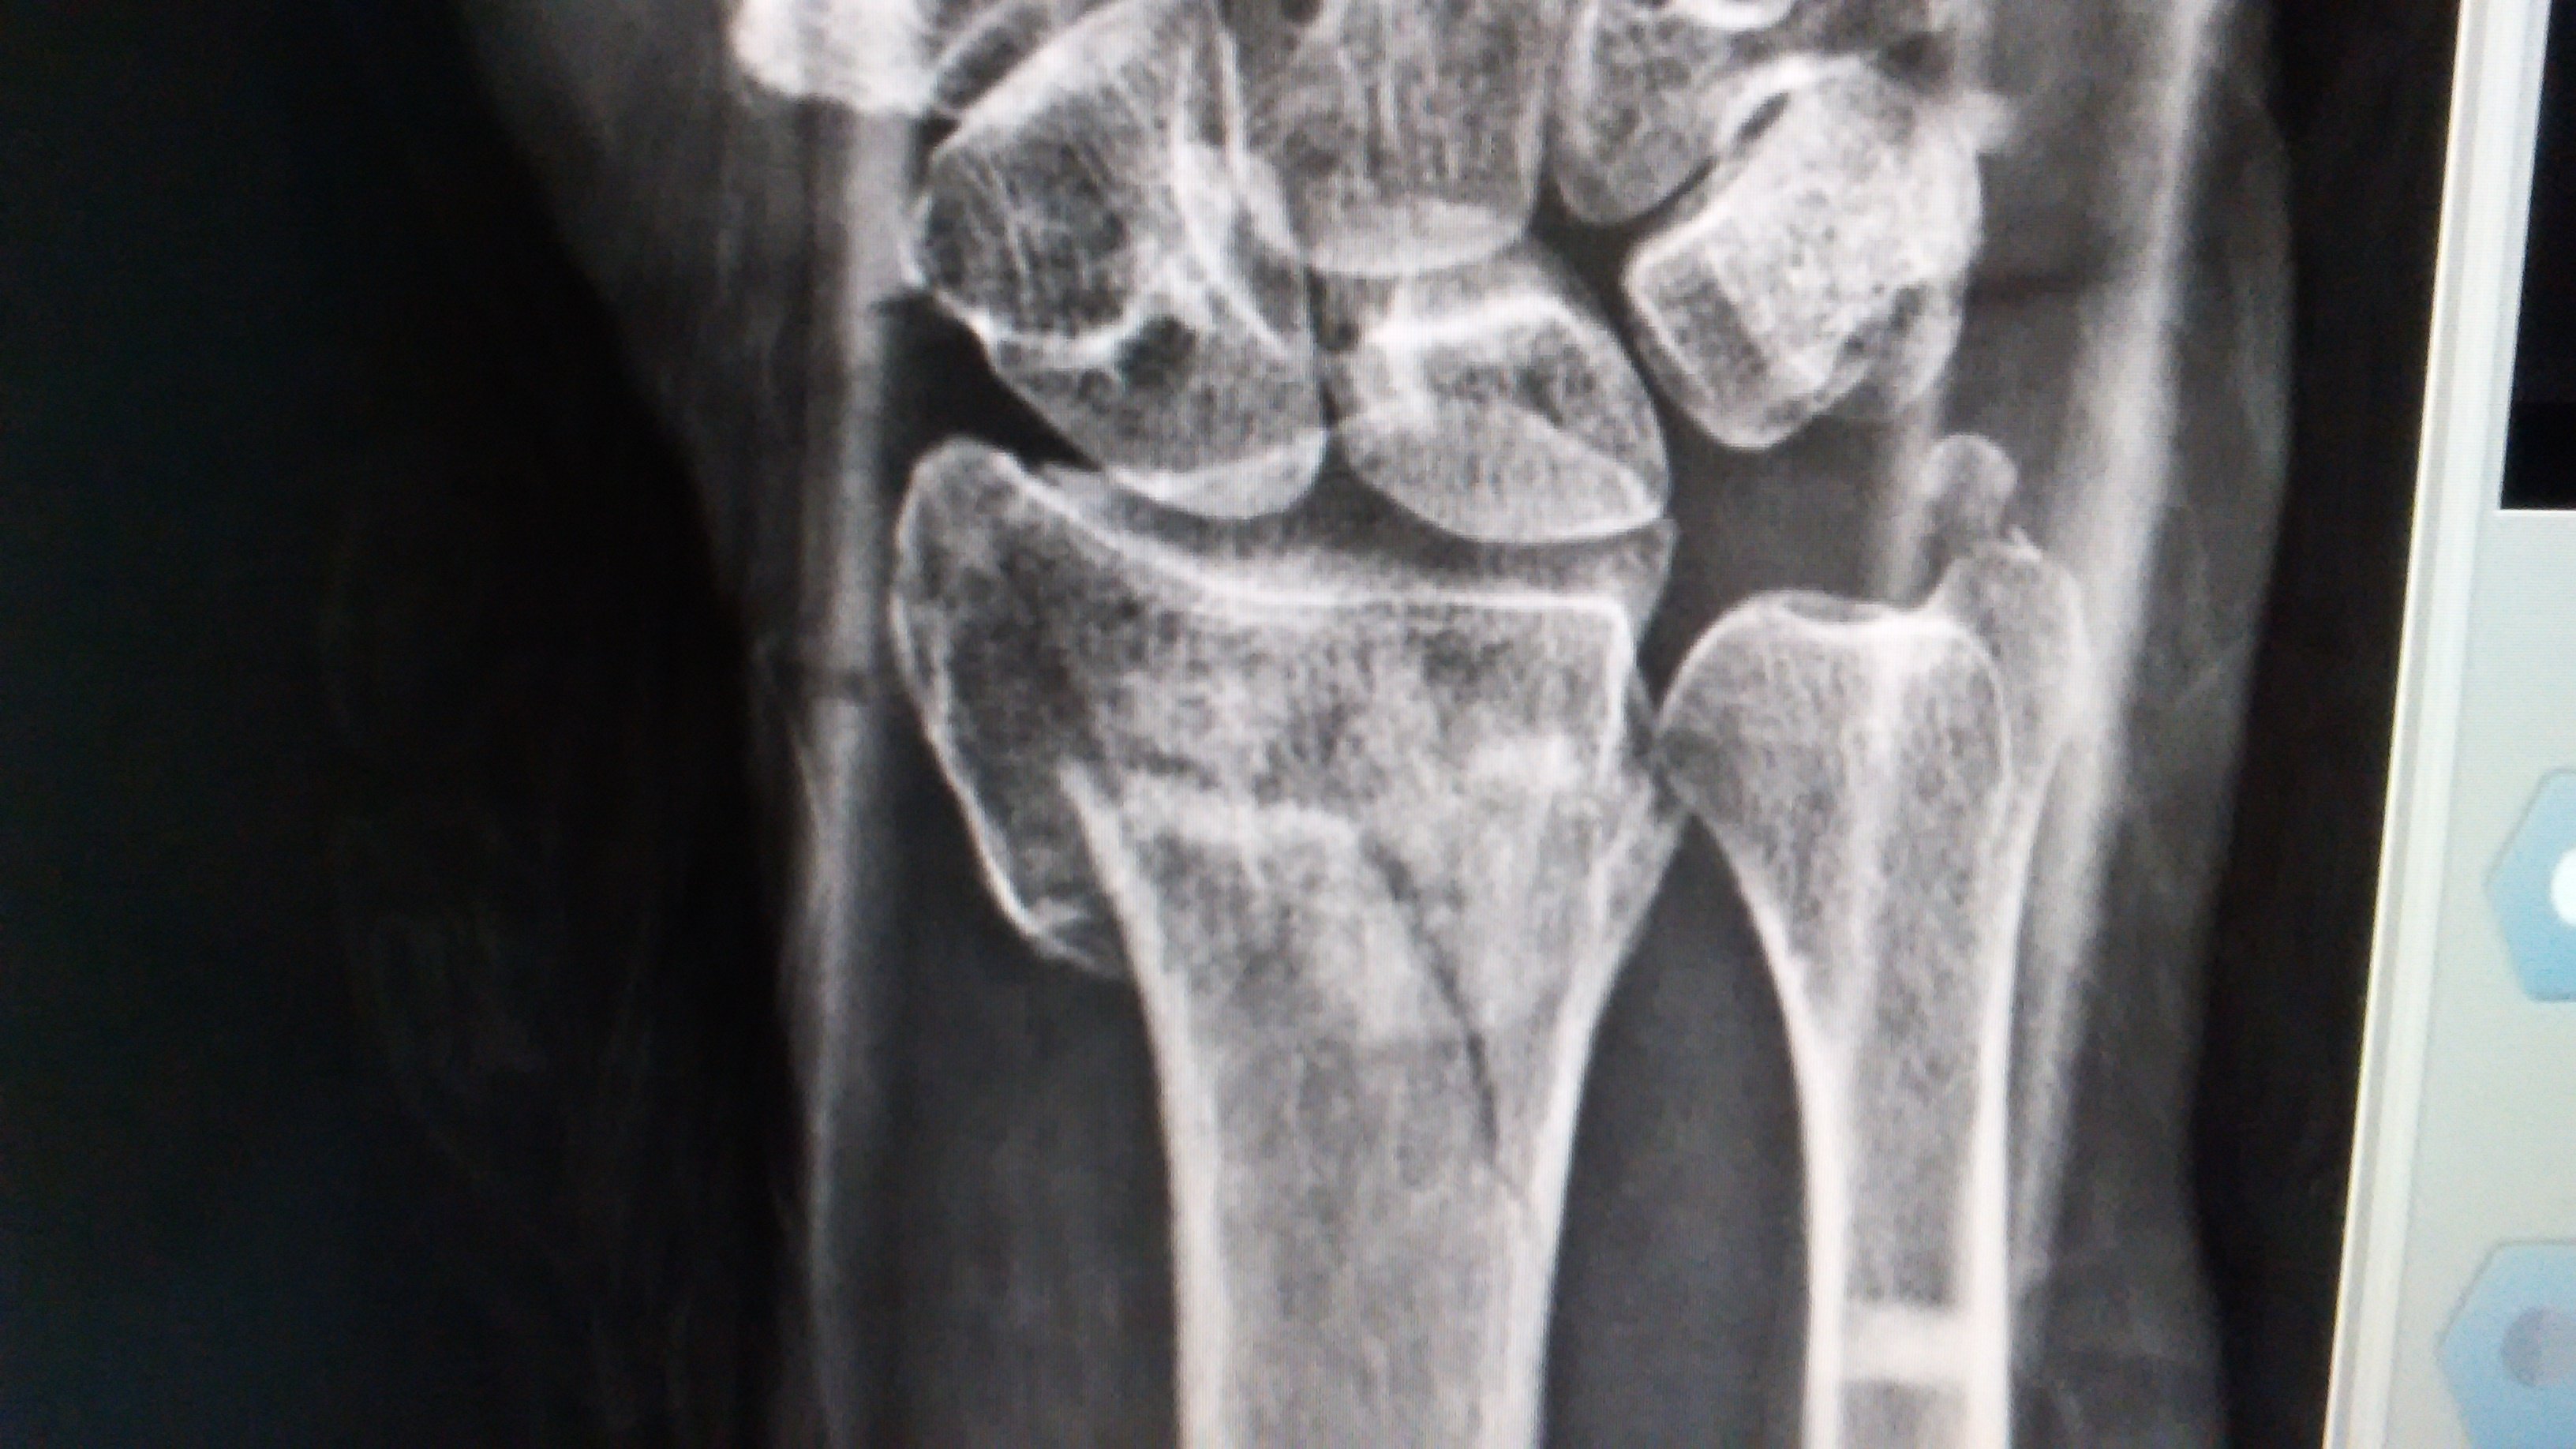

Wrist fractures are varied, ranging from a simple, non-displaced and stable fracture to complex, multiple and displaced fractures.

IMG_20151007_182817.jpg